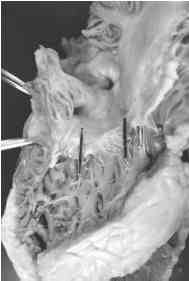

Figura 1: Preparación anatomopatológica. Cavidad auriculoventricular derecha. Las señales corresponden al área del nodo AV de las figuras 3 y 4.